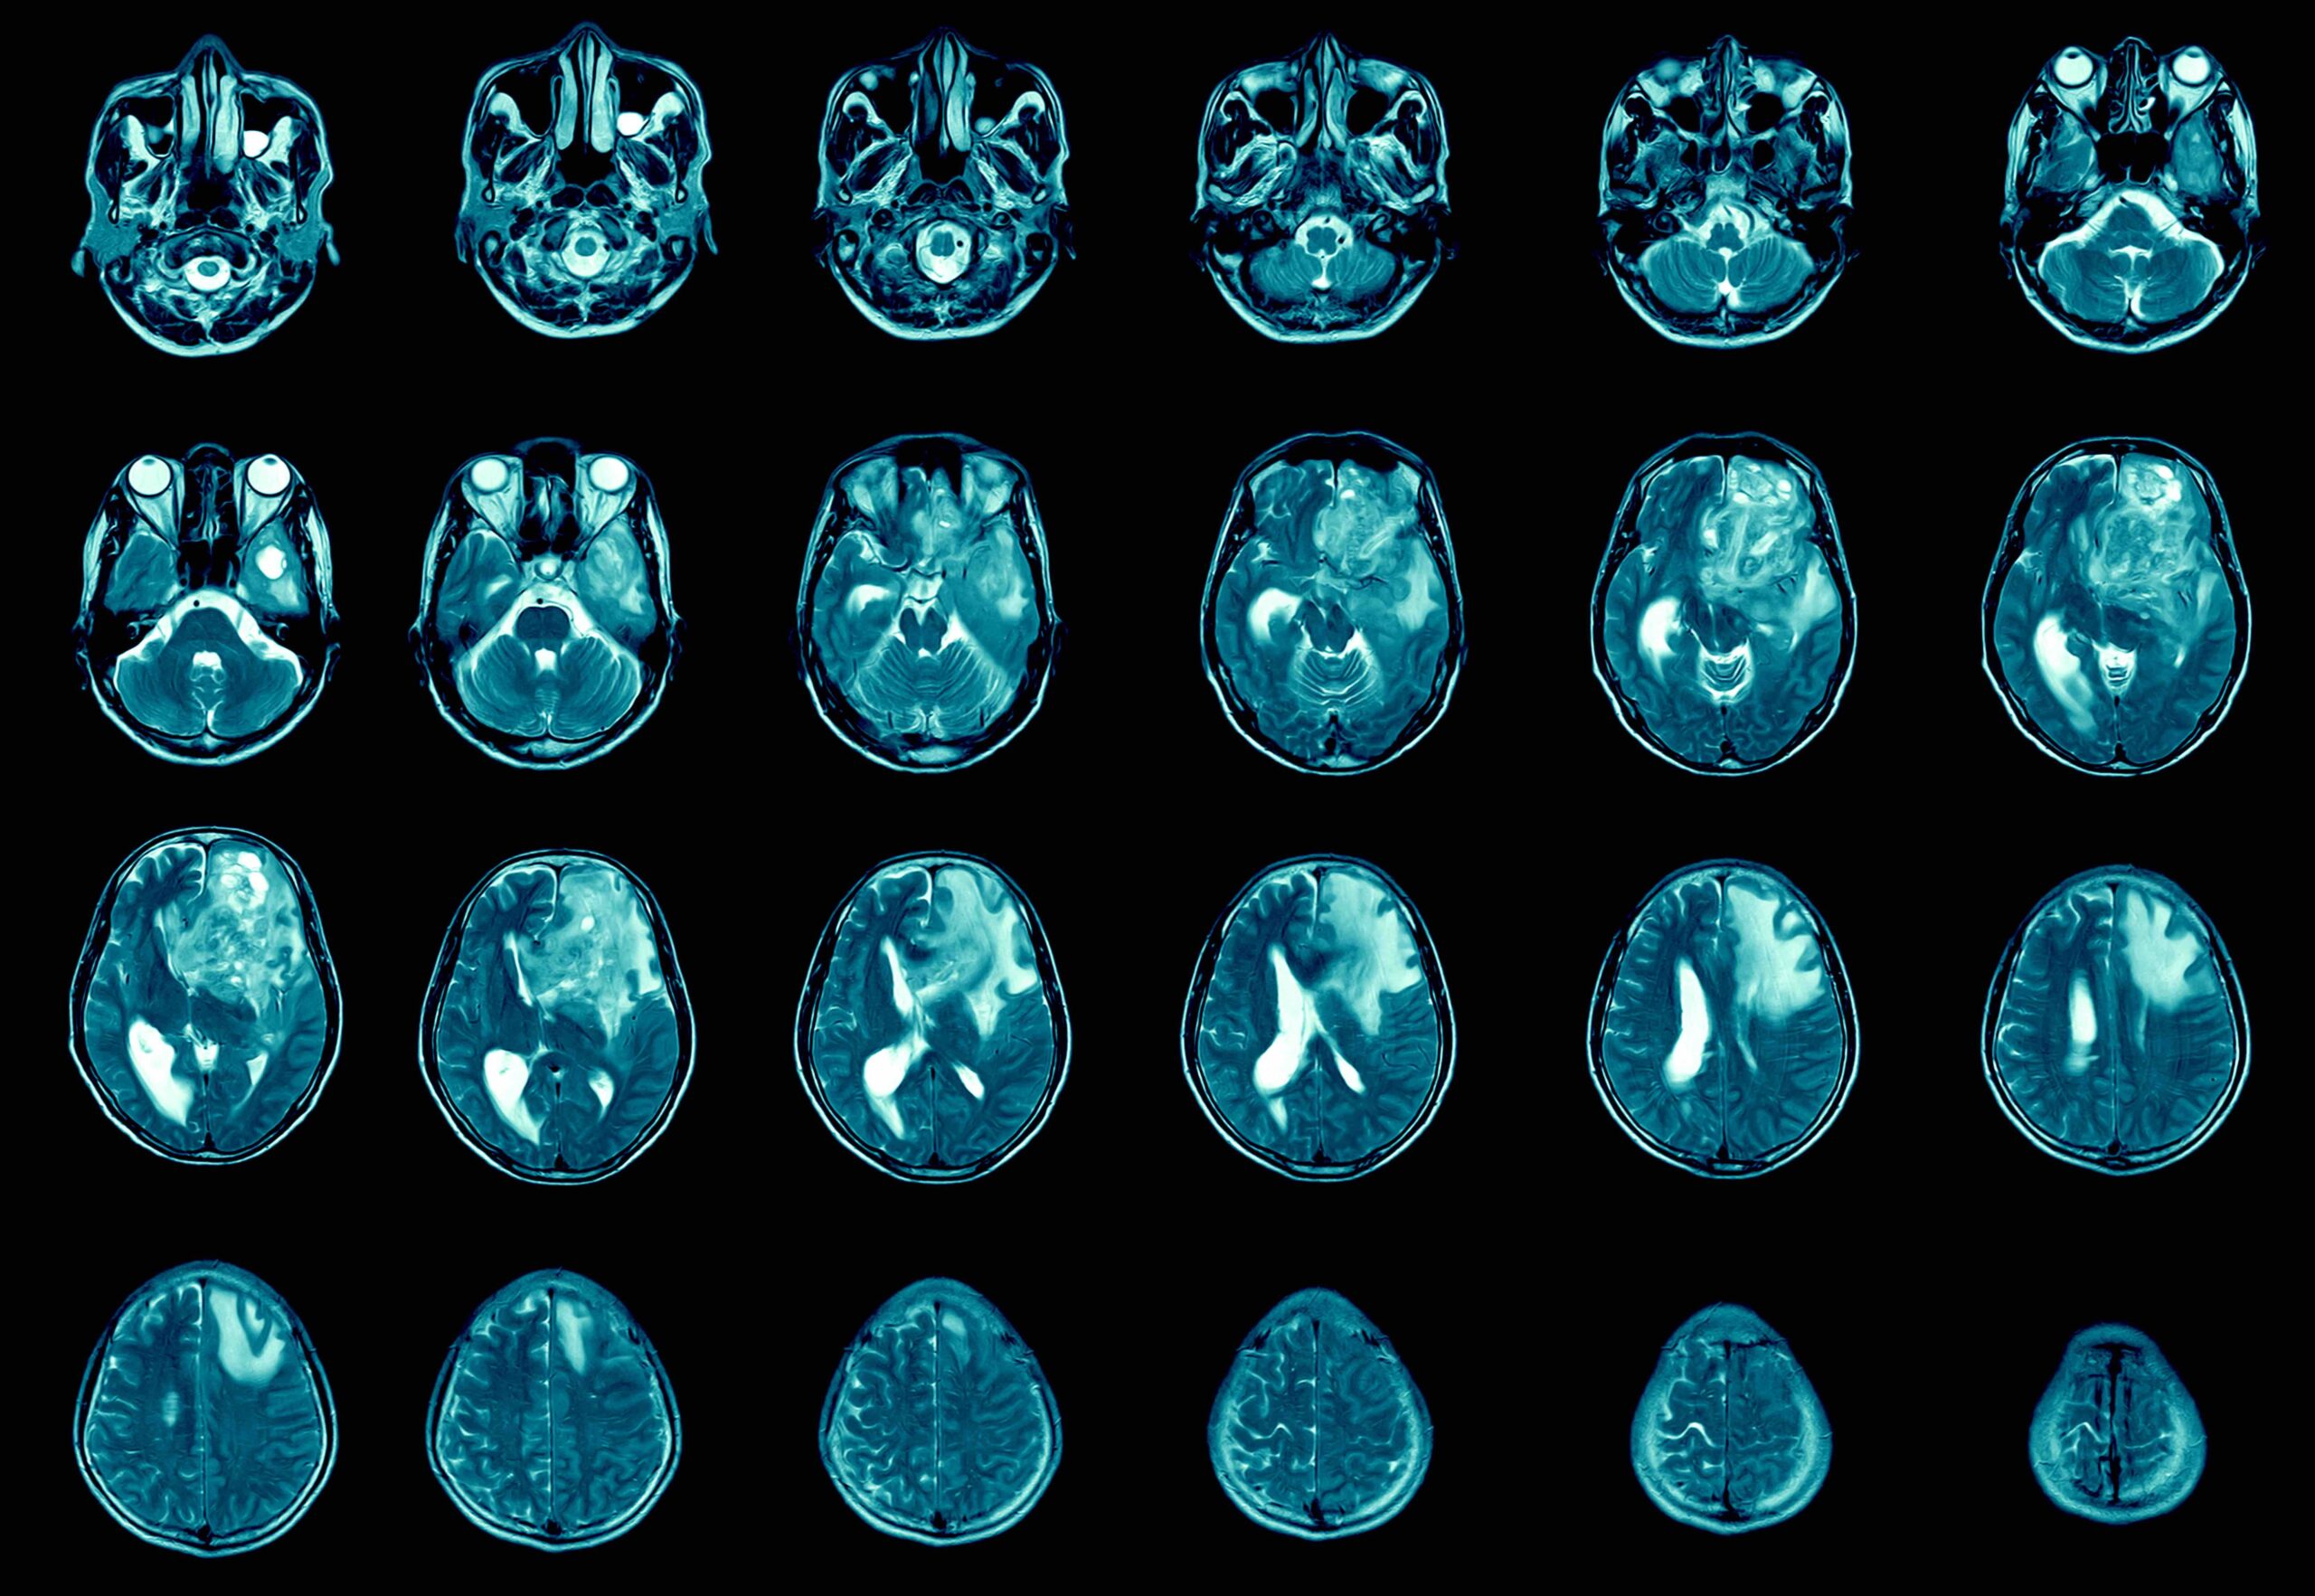

Das Glioblastom ist ein verheerender Hirntumor. Hilft Cannabis?

Das Glioblastom ist ein verheerender Hirntumor, der schnell wächst und in das umliegende Hirngewebe eindringt. Es ist der am weitesten verbreitete Hirntumor bei Erwachsenen und betrifft jedes Jahr etwa 12.000 Amerikaner. Das Überleben nach der Diagnose beträgt im Allgemeinen 15 bis 18 Monate. Die 5-Jahres-Überlebensrate von Patienten mit Glioblastom beträgt 5 %. Aufgrund dieser düsteren Prognose sind sich Kliniker einig, dass ein dringender Bedarf an einer Heilung besteht.

Das Glioblastom beginnt in sternförmigen Gliazellen, die Astrozyten genannt werden. In gesundem Gewebe spielen Astrozyten eine wichtige Rolle bei der Bildung und Regulation von Synapsen zwischen Neuronen. Aufgrund ihrer Bedeutung können fehlerhafte Astrozyten jedoch große Probleme verursachen.

Bei Patienten mit Glioblastom bilden krebsartige Astrozyten einen schnell wachsenden Tumor. Die derzeitige Behandlung des Glioblastoms umfasst eine Operation, gefolgt von Bestrahlung und Chemotherapie. Trotz Behandlung wächst der Tumor wieder und 95 % der Patienten sterben innerhalb von fünf Jahren nach ihrer Erstdiagnose.